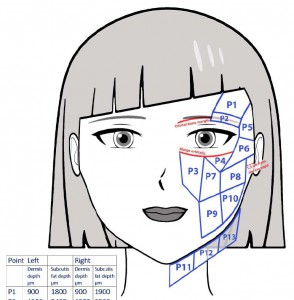

Εφαρμογές αισθητικής ιατρικής

-Έγχυση Πληρωτικών Υλικών (Fillers)